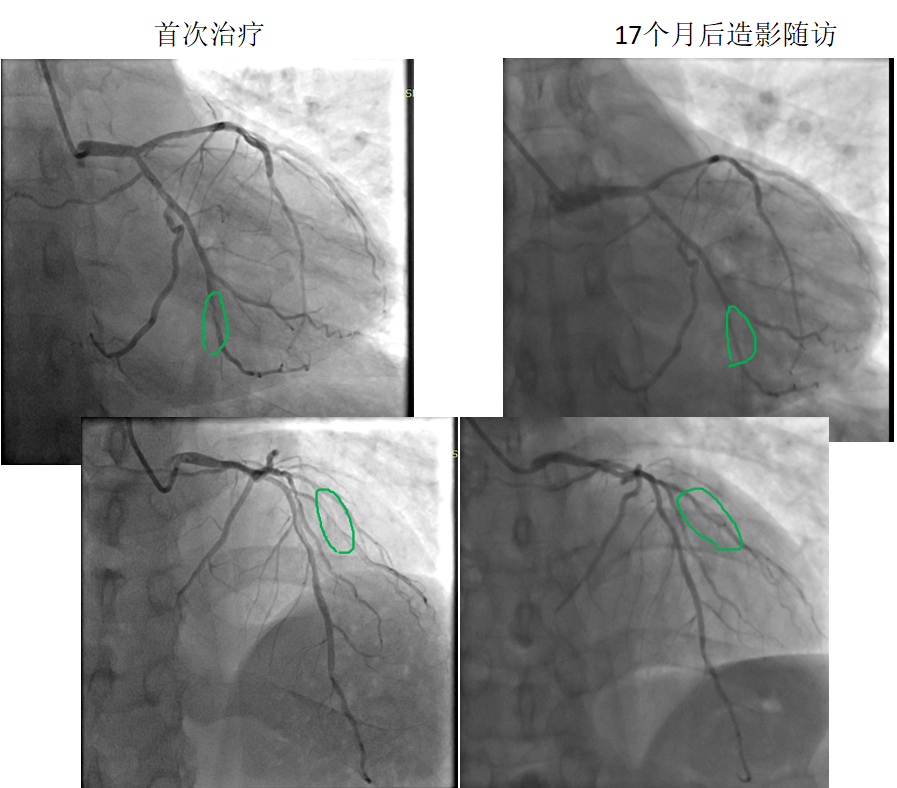

病變部位: OM中遠(yuǎn)段95% ;D1近段90%

使用藥物球囊:2.0 x 20mm; 2.0 x 20mm

17個月后造影隨訪:OM中遠(yuǎn)段20% ;D1近段20%

藥物球囊治療原位病變(圖1)